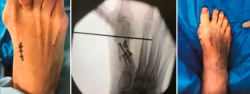

Figura 2. Detalles quirúrgicos de la osteotomía de apertura medial.

No se objetivó ningún caso de metatarsalgia de transferencia ni de pseudoartrosis. En las Figuras 2 y 3 se pueden ver detalles quirúrgicos de las osteotomías de apertura y cierre.

La cirugía se realiza con raquianestesia o bloqueo locorregional de la pierna, acompañados de isquemia distal a la rodilla, y consiste en un primer tiempo de partes blandas distales (buniectomía, sección aductor, plicatura capsular final) y osteotomía proximal (cierre o apertura) con sierra oscilante. Después, se intenta una osteoclasia sin desplazamiento para, posteriormente, forzar la posición de flexión plantar del primer metatarsiano ayudándose, si es preciso, de una fijación transitoria con una aguja de Kirschner (entre el primer y el segundo metatarsiano). Para la síntesis, se utiliza una placa de escalón en las osteotomías de apertura y 2 tornillos de 2,6 mm en las de cierre (excepto en 2 casos en los que se utilizaron placas). Por último, se coloca vendaje estándar de antepié permitiendo la carga inmediata con zapato ortopédico rígido plano sin tacón durante 6 semanas. Los detalles postoperatorios se indican en la Tabla 1.